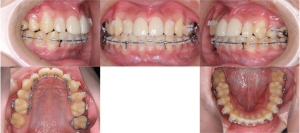

※初診時口腔内写真正面

青色の矢印で示している部分を見ると、歯と歯の間にすき間がある状態であることがわかります。

白い線で上の前歯の形をなぞってみると、歯の大きさや形のバランスに乱れがあることが確認できます。

また、黄色い丸で囲んだ部分には、**上唇の内側と歯ぐきをつなぐヒダ(上唇小帯)**が見られます。このヒダが発達している場合、上の前歯の間にすき間ができやすくなることがあります。

※前歯の噛み合わせ

下の前歯が、上の前歯の歯ぐきに触れそうになるほど深い噛み合わせであることが確認されました。このような噛み合わせは、下あごがやや小さい場合に見られることがあります。